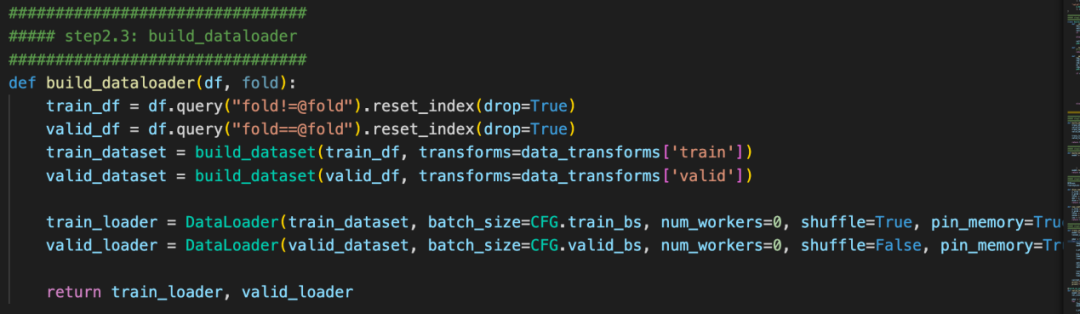

4、baseline

本次提供的baseline分为hypre-parameter, data, model, Loss, train五个方面。

整套baseline的代码非常清晰, 非常适合入门以及后续代码复用。